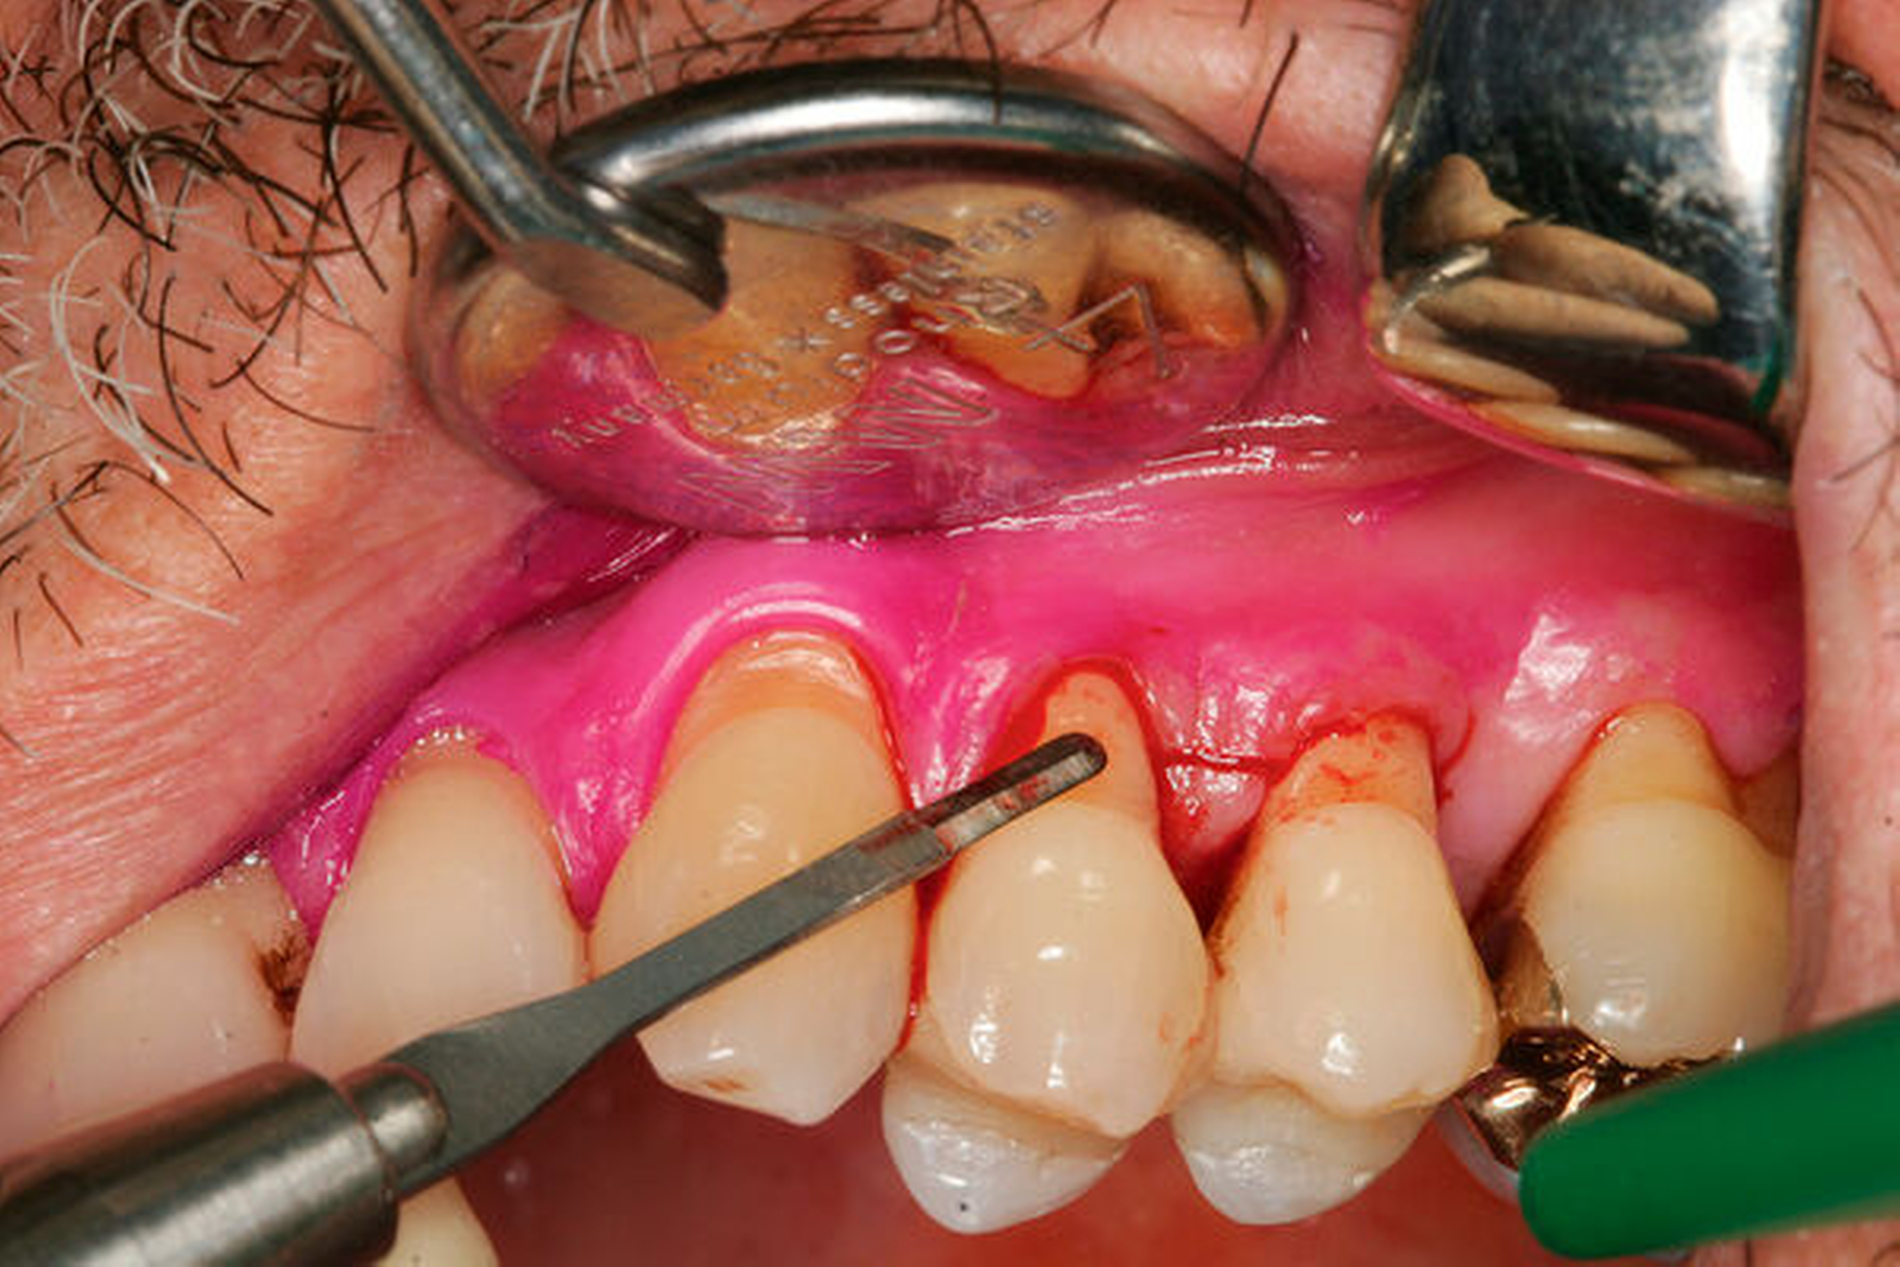

Werden verschiedene Zugangslappentechniken wie Instrumentierung unter Sicht mit Lappenbildung (Open Flap Debridement, OFD), Lappen mit paramarginaler Inzision (modified Widman Flap, MWF, Abbildungen 1 und 2), und Papillenerhaltungslappen (Abbildung 3) als konservative parodontalchirurgische Interventionen ohne signifikanten Weich- und Hartgewebsverlust hinsichtlich der Reduktion der TST verglichen, so bestehen kaum Unterschiede. MWF und OFD wurden in drei randomisierten klinischen Studien verglichen und nur eine davon hatte eine höhere Taschensondierungstiefenreduktion durch den MWF zum Ergebnis [Sanz-Sanchez et al., 2020].

Diese Fragestellung in der Leitlinie widmet sich dem Vergleich der Ergebnisse nach Lappenoperation mittels Zugangslappen (Abbildung 3), also Lappenbildung ohne gezielten Gewebsverlust, und resektiver Parodontalchirurgie – mit gezieltem Gewebsverlust, jedoch ohne zusätzliche Materialien zur parodontalen Regeneration [Polak et al., 2020]. Dabei werden alle chirurgischen Verfahren mit Resttaschen ab 5 mm nach vorheriger subgingivaler Instrumentierung verglichen. Bei der Betrachtung werden MWF (Abbildung 1), Excisional New Attachment Procedure (ENAP) in der Gruppe der Zugangslappen geführt. Die Gruppe der resektiven Parodontalchirurgie besteht aus auch zum Teil älteren Verfahren mit deutlicher Veränderung der Gingiva- und der Knochenkontur.

Dieser Empfehlung liegen zwei systematische Übersichtsarbeiten zugrunde [Graziani et al., 2012; Nibali et al., 2020]. Durch einen Papillenerhaltungslappen lassen sich höhere CAL-Gewinne und TST-Reduktionen erreichen. Im Vergleich zur Instrumentierung unter Sicht (Zugangslappenoperation) führt diese Technik zu geringeren postoperativen Rezessionen. Die erhöhte Komplexität dieser Methode bedarf allerdings zusätzlichen Trainings. (Abbildung 4).